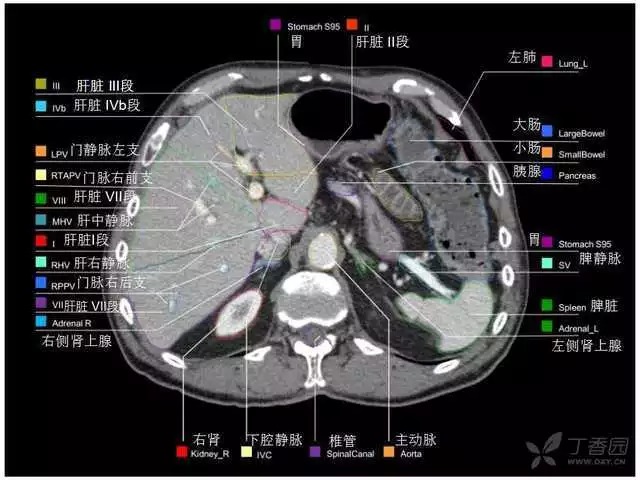

腹部肝脏高清CT断层的图谱

全腹部高清CT图谱,淋巴结彩色图谱,血管解剖图谱大汇总!

超声肝脏分叶及分段

肝脏分段和基本解剖学标志